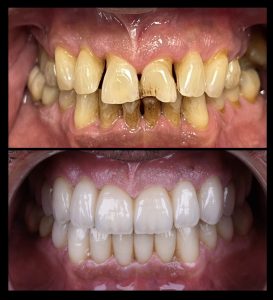

Estetska Stomatologija

Savremena estetska stomatologija koristi materijale vrhunskog kvaliteta koji verno imitiraju prirodan izgled zuba